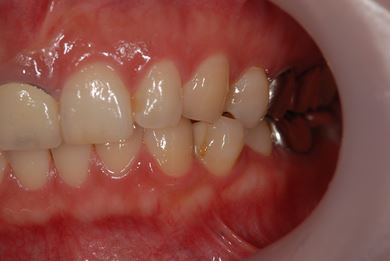

| 性別/年齢 | 女性 / 38歳 | ||||||||||||||||||||||||||||||||

| 主訴 | 右奥歯2本、インレーの相談をしたい。 | ||||||||||||||||||||||||||||||||

| 治療方針 | セラミック治療にて、審美的回復を行う。 | ||||||||||||||||||||||||||||||||

| 治療内容 | ハイブリッドセラミックインレー2本、メタルボンドセラミッククラウン2本(メタルボンド用土台2本)、オールセラミッククラウン1本(オールセラミック用土台1本) | ||||||||||||||||||||||||||||||||